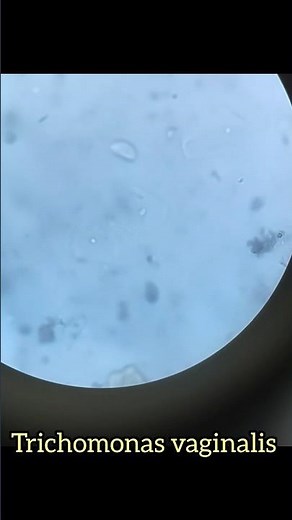

- HIV/

AIDS - Trichomonas Vaginalis

Under Microscope - HPV